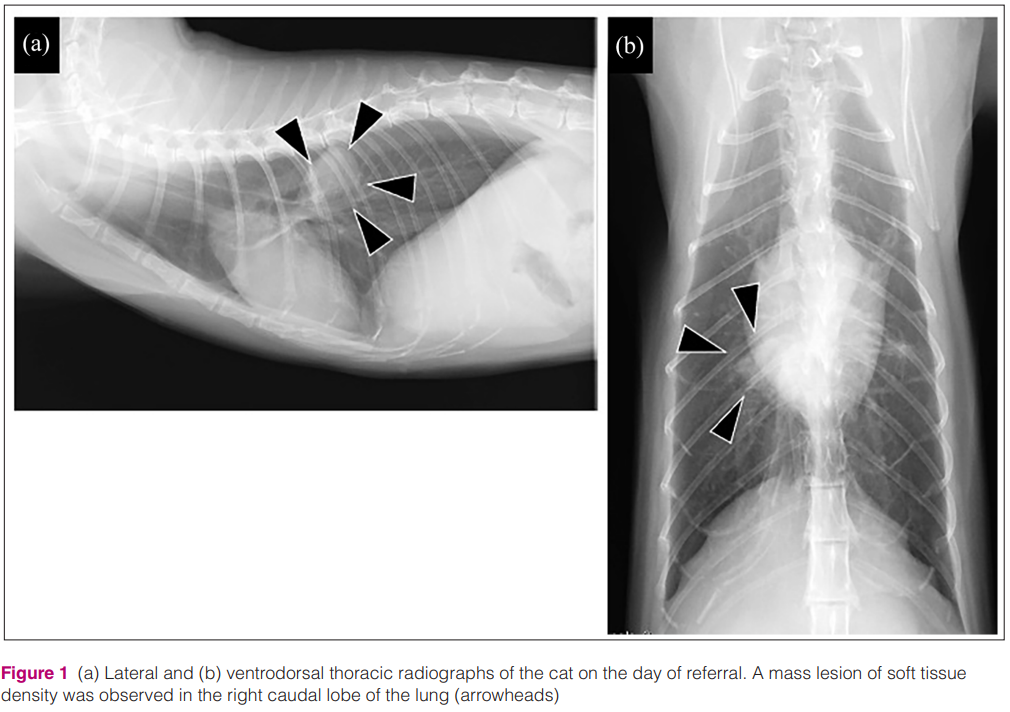

폐 종양이 잘 발생하는 우측 폐 후엽부 종괴성 병변이 있었는데

CT 촬영을 해보니

조영상에서 낭성 구조를 가지고 있어서 폐종양의 가능성은 낮아졌지만 실제 무엇인지 알기 위해 FNA를 CT 가이드로 했다는 것.